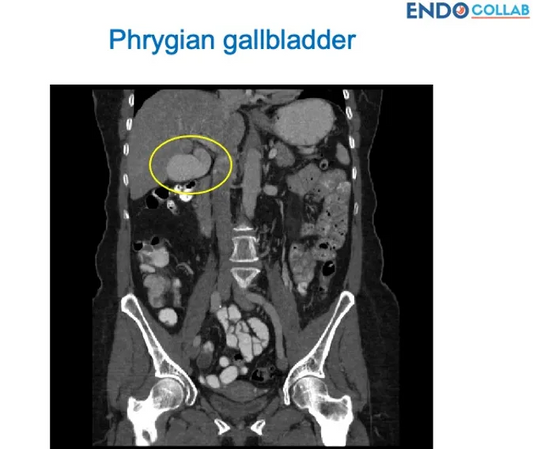

Understanding the Phrygian Cap Gallbladder: Com...

Explore the Phrygian cap gallbladder, a congenital abnormality found in 4% of the population. Learn about its appearance on imaging, its non-pathological nature, and when medical intervention might be necessary.